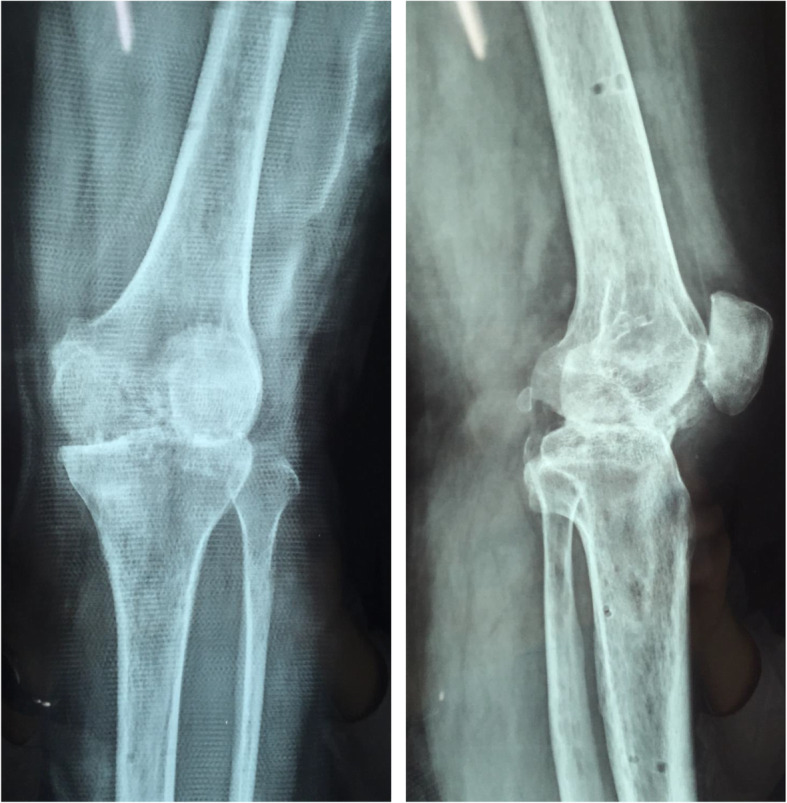

Fig. 1.

X-ray (anteroposterior and lateral): clearly osteoporosis, uneven joint space narrowing, and joint bone destruction